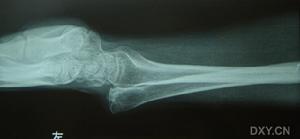

前臂外傷後疼痛活動障礙,X線片可明確骨折類型及移位情況。照片應包括肘腕關節,以了解有無鏇轉移位及上下尺橈關節脫位。

尺橈骨幹骨折本病根據其外傷病史及臨床表現可以初步確診,但還應使用一些輔助檢查的方法幫助進一步診斷,X線片可明確骨折類型及移位情況。照片應包括肘、腕關節,以了解有無鏇轉移位及上、下尺橈關節脫位。